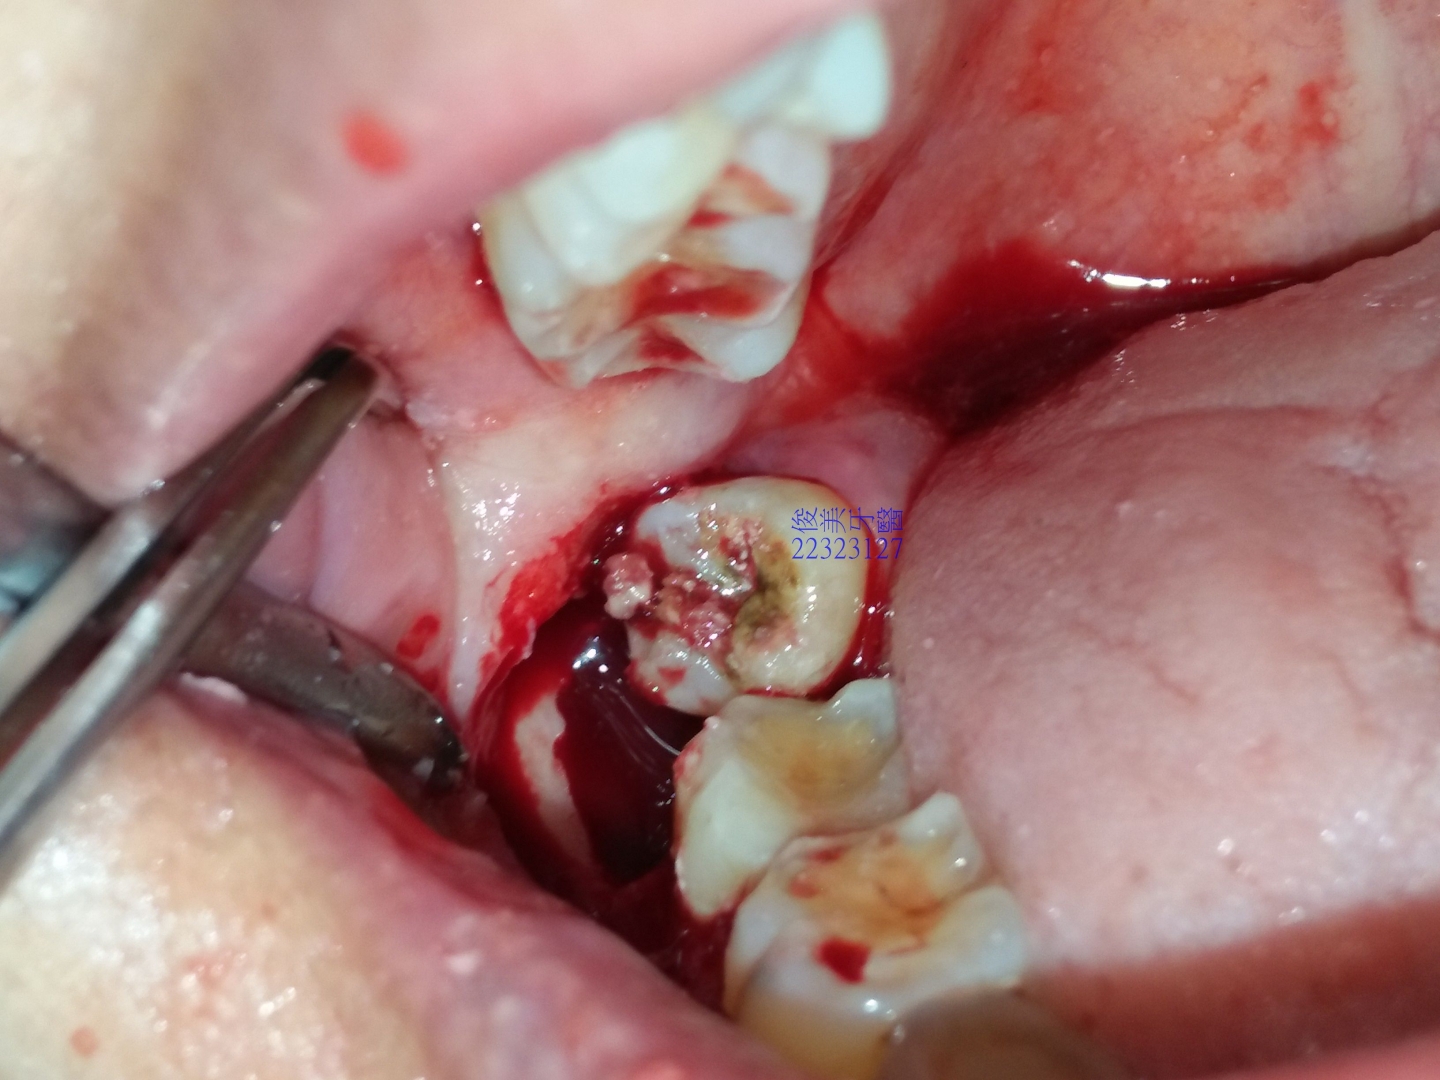

醫師一將牙冠上抬就發現塞的一塌糊塗,患者沒有認真清潔,導致食物殘渣只進不出,牙冠已有蛀牙現象,

塞久了,當然可能會發炎......

且也影響了前一顆牙的臨界牙縫.......